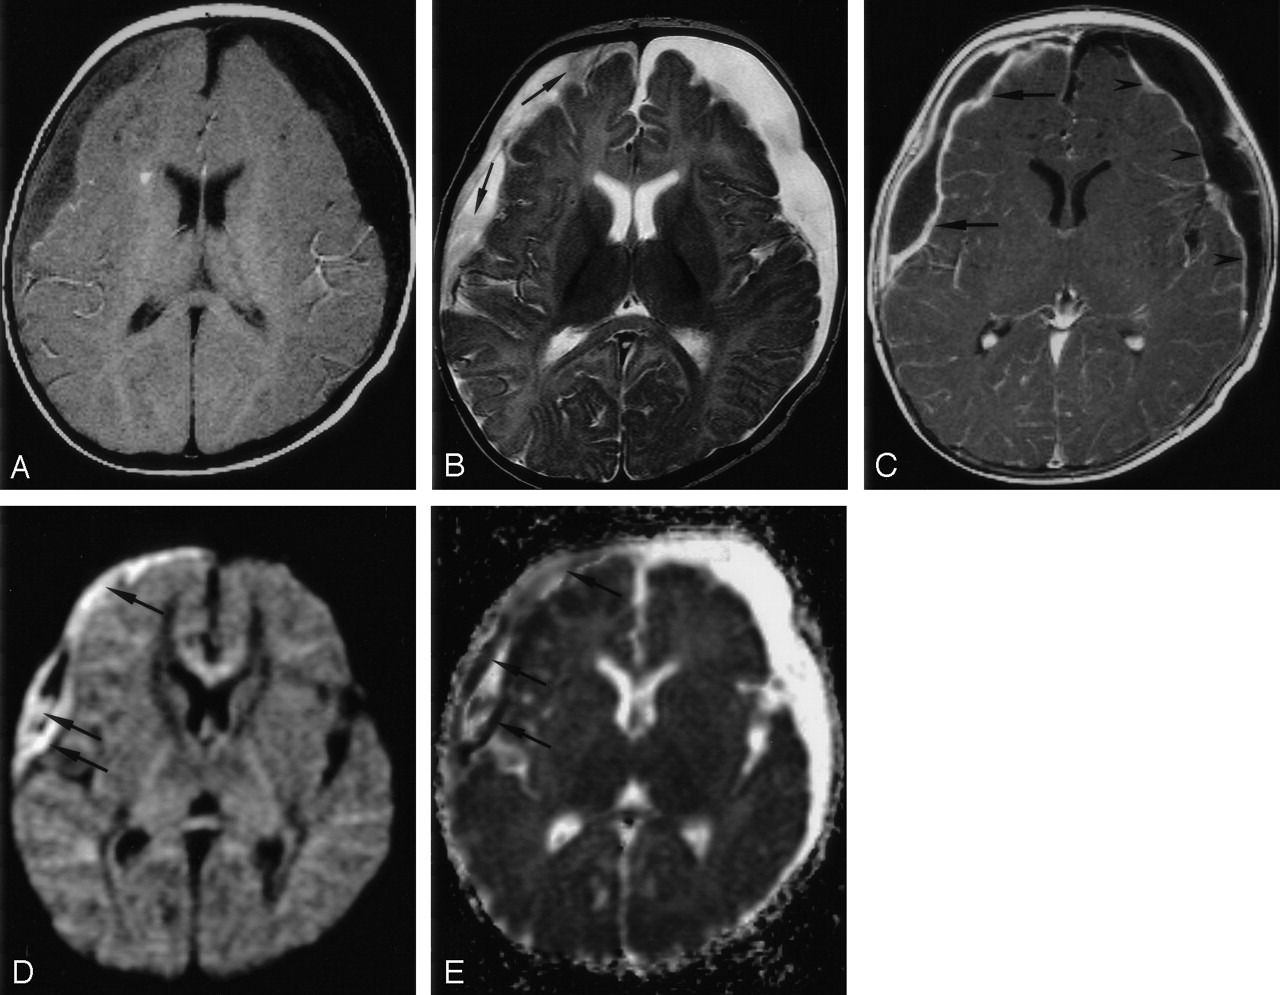

All 10 patients had reduced water diffusion in their SDE (Table 2). On DWIs, SDE showed high signal intensity in nine patients (90%) (Fig 1) and mixed hyperintensity and hypointensity in one (Fig 2). The mean ADC value of the seven SDE was 0.604 ± 0.18 mm2/s (mean ± SD) and lower than that of normal cortical gray matter (1.029 ± 0.175 mm2/s; P = .001). On T1WIs, the SDE were isointense in five patients (50%) (Fig 1), mildly hypointense in one (10%), and hypointense in four (40%) (Fig 2). On T2WIs, they were hyperintense in five patients (50%) (Fig 2), mildly hyperintense in four (40%), and isointense in one (10%) (Fig 1). Postcontrast T1WI showed smooth, linear, capsular enhancement in nine patients (90%) with SDEs (Fig 1) and irregular capsular enhancement in one (10%). The SDE showed mass effect on brain parenchyma in eight patients (80%).

Patient 8. Bifrontal and right parafalcine SDE.

A. Axial T1WI (650/14) shows slight hypointensity in the SDE (arrows).

B, Axial T2WI (6000/99) shows intermediate signal intensity in the bifrontal collections (arrows) and hyperintensity in the right parafalcine collection (arrowheads).

C, Coronal contrast-enhanced T1WI (800/20) with MT shows irregular capsular enhancement of the collections (arrows).

D and E, Axial DWI (4000/110, b = 1000 s/mm2) and ADC map show reduced water diffusion in the SDE.